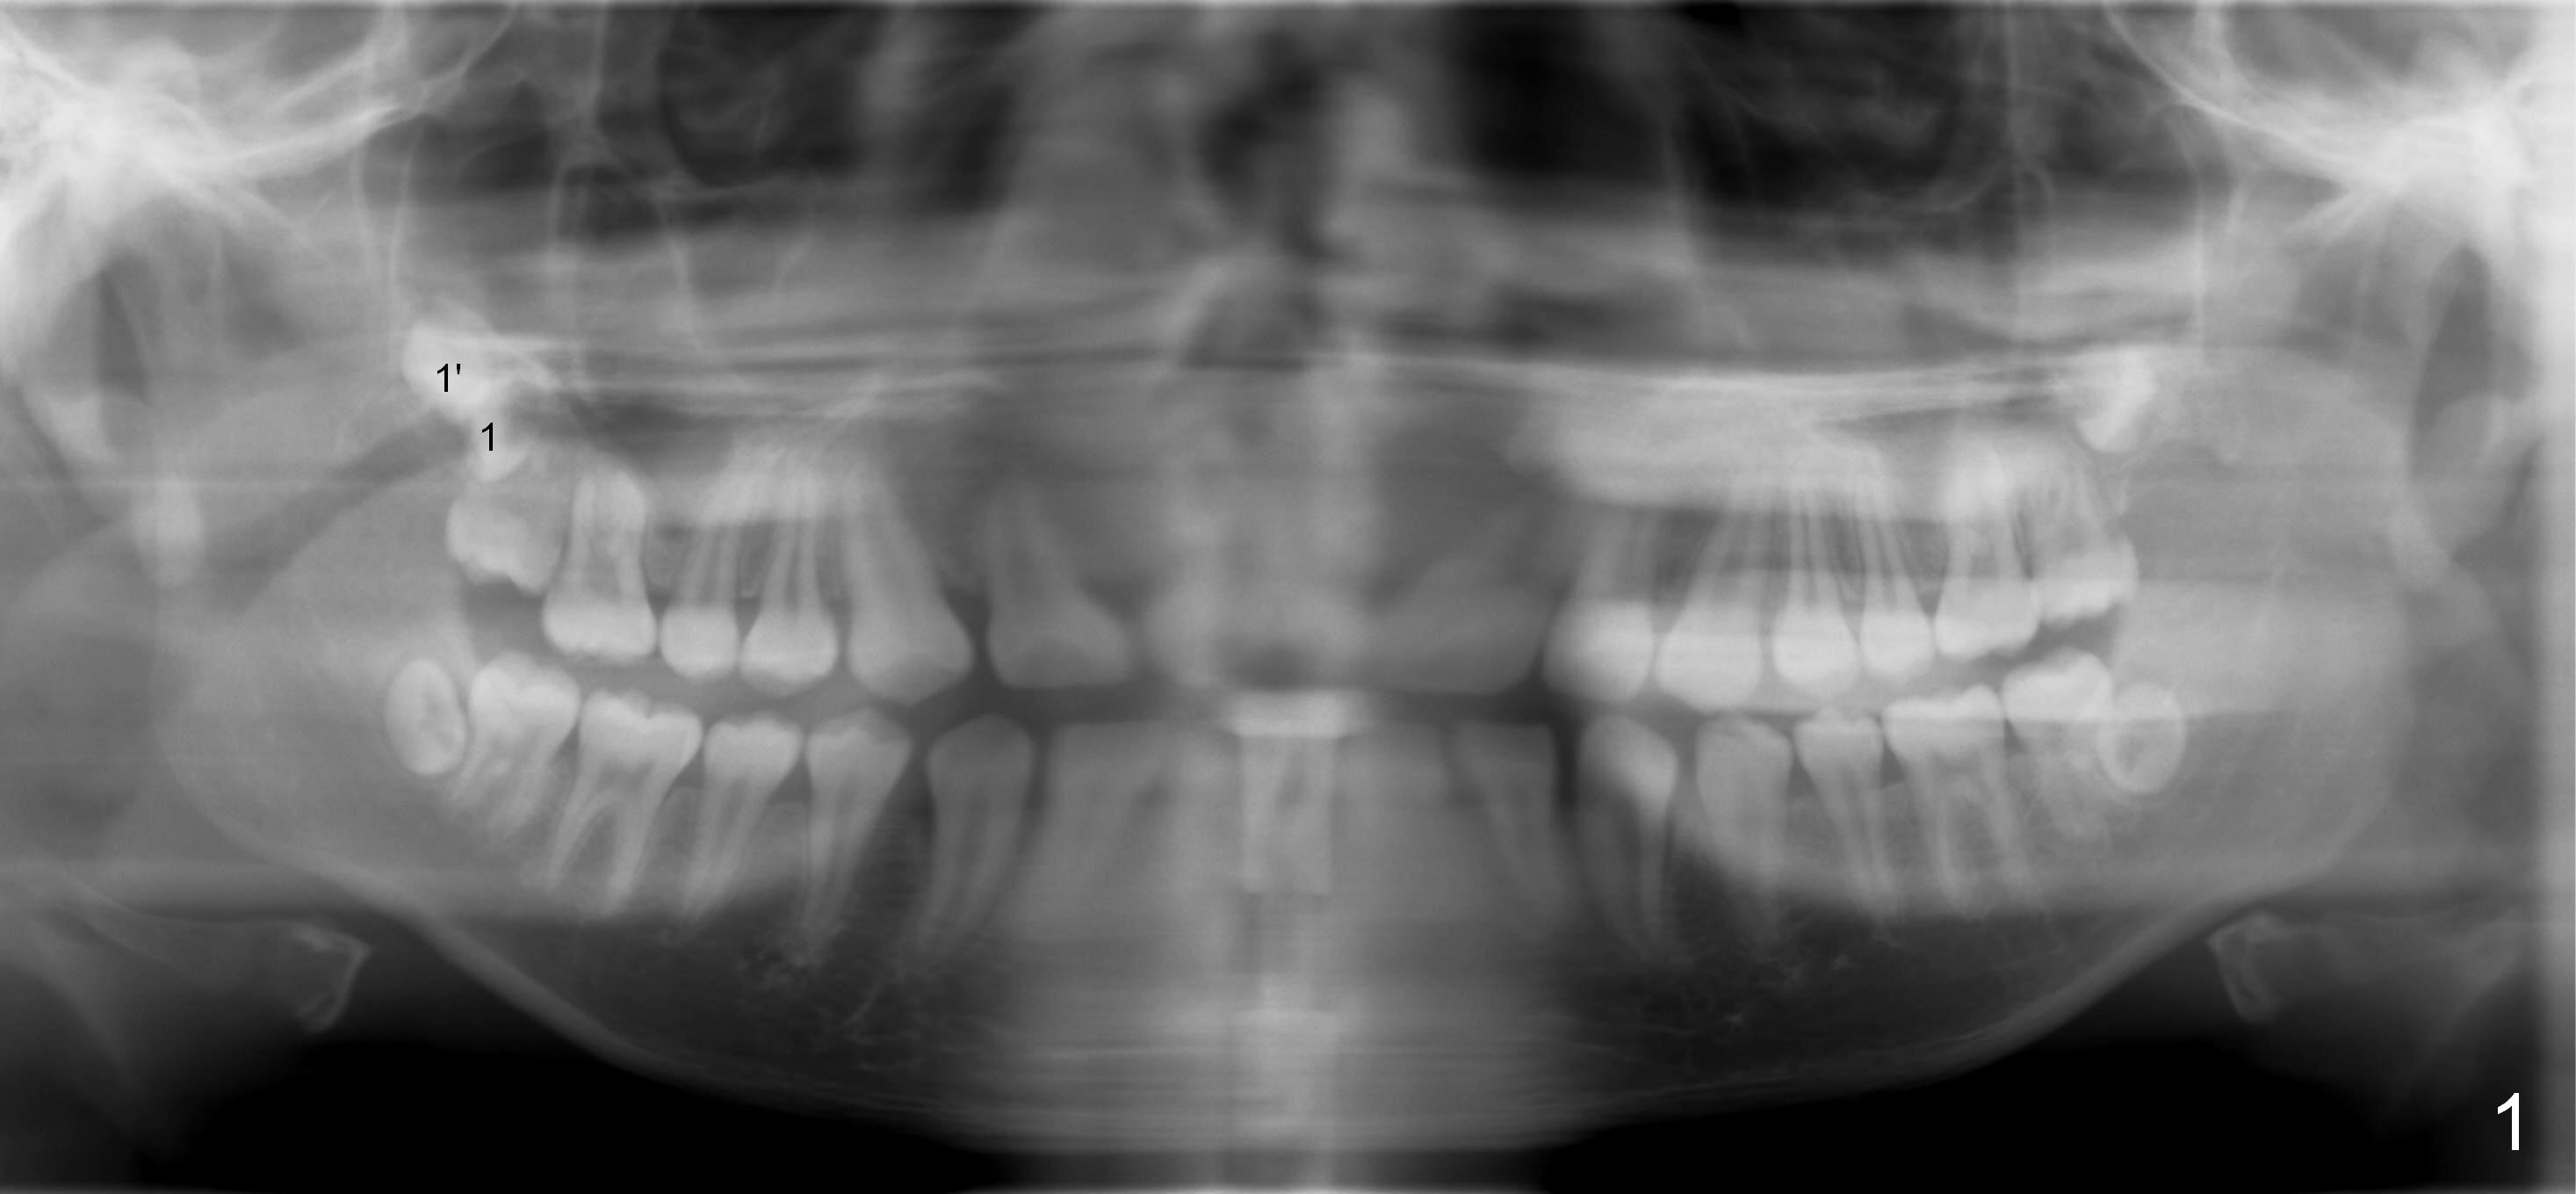

A 18 year old man has fully developing jaws.  It appears that there is enough room for 4 3rd molars to erupt normally.  In fact, the teeth #16,17,32 erupt.  Attached are pan taken 2 and 5 years ago (Fig.2,1, respectively).  I wonder whether we can take out one of the upper right 3rd molars and let the other erupt.  If the latter does not happen, #1 and 32 will be extracted.  The teeth #16 and 17 are not to be extracted.  Due to insurance limitation, the pan is not updated.  Thanks.

Now regarding this case.  No surgeon will take out wisdom teeth in a growing patient, which he is (the teeth anyway), without a current panx. So you are diagnosing from a weak position.  Regardless, you can see he has two #1 teeth--supernumerary.  It is clear the lower molars are mesial angularly impacted, with no hope of full eruption.  The upper wisdom teeth are still positioned high above the CEJ of the second molars, making removal difficult and traumatic.  But this is an old X-ray and we cannot make judgments because we know the roots are longer and the upper teeth have probably migrated more coronally.